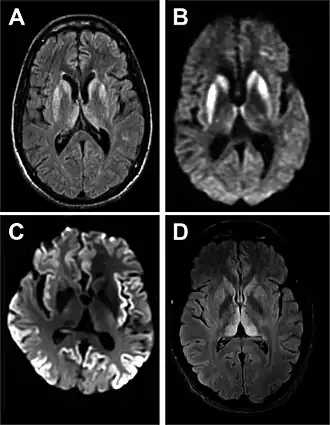

| Ressonância magnética de DCJ esporádica[2] | |